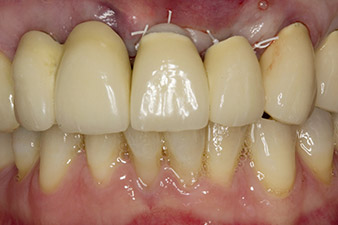

pilot drilling is performed with the new Implantmed and the WS-56 L contra-angle handpiece

Fig. 2: Two months later the pilot drilling is performed with the new Implantmed and the WS-56 L contra-angle handpiece (programme P1, ratio 1:1). The cooling is performed via the spray tube positioned on the left (for right-handed users).